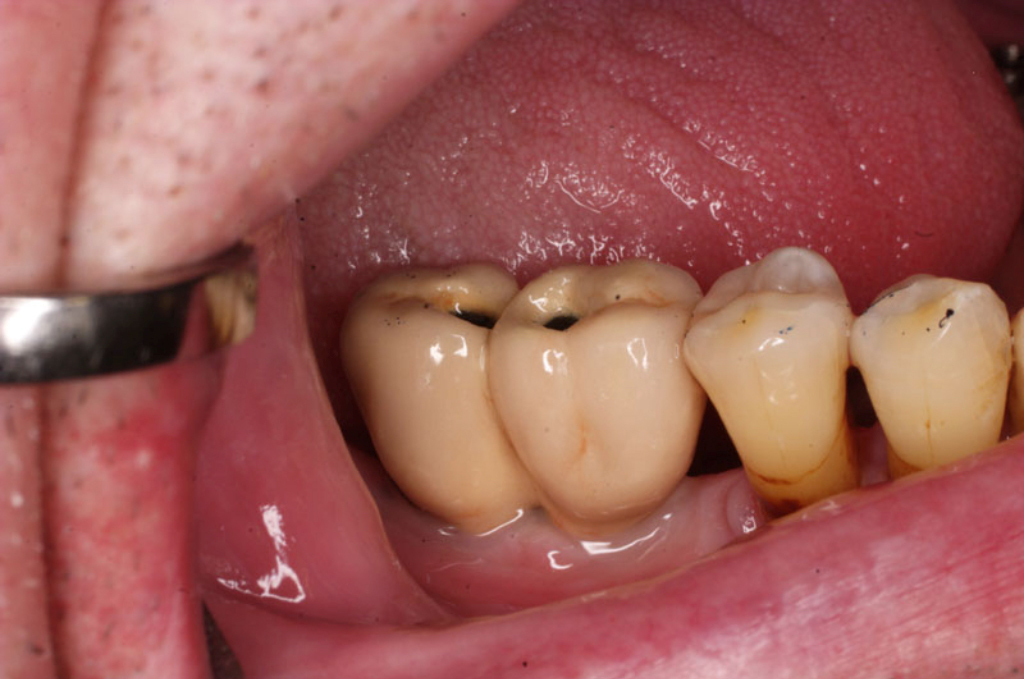

Částečně ozubená čelist

V případě chybění většího počtu zubů v postranních úsecích čelistí je možné ošetření pomocí implantátů, které nahradí ošetření pomocí snímacích náhrad kotvených na zbývajících zubech nebo patře.

Podmínkou je opět dostatečné množství kosti.

Protetické řešení může být pomocí můstku, který je kotvený na implantátech nebo pomocí jednotlivých korunek na implantátech.

V zásadě je možné do těchto můstků zařadit i přirozené zuby, zejména pokud je potřeba tyto zuby ošetřit proteticky – korunkami. Korunky nebo můstky mohou být na implantáty nacementovány nebo přišroubovány.

Zdravé zuby zůstanou zachovány a přitom náhrady jsou pevné, jako na vlastních zubech